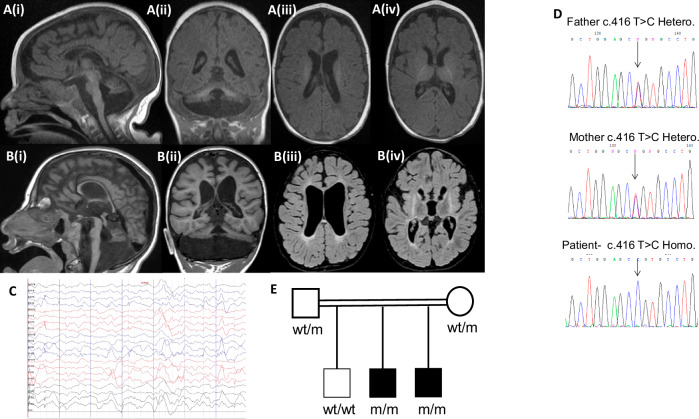

Fig. 1 Clinical data of the proband and his family.

A Brain MRI of proband performed at aged 5 months (T1-weighted image: i – sagittal, ii – coronal, iii/iv – axial) demonstrating prominent hypoplasia of all cerebellar structures, hypoplastic pons, generalized mild cerebral atrophy, thin corpus callosum, and delayed myelination. B Brain MRI of proband’s brother aged 4 years, 5 months. (T1-weighted image: i – sagittal, ii – coronal) demonstrating profound hypoplastic cerebellum including the vermis and the pons with a thin corpus callosum. Axial T2/FLAIR- weighted image (iii/iv) shows brain atrophy, diffuse diminished white matter, very small basal ganglia with high T2/FLAIR signal signifying damage/gliosis, with preserved thalamus structure. C Inter-ictal EEG recording from the proband demonstrating dysrhythmia and multifocal epileptiform activity. D Chromatograms of the proband and his parents. Top – the heterozygous parents, bottom – the homozygous proband. E Pedigree of affected family. Solid black squares indicate affected individuals, wt – wild type, m - c.416T > C MED29 variant.